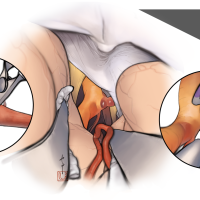

術後イラストシリーズ

監修:太田 仲郎

脳神経外科速報2023vol.33(メディカ出版)寄稿シリーズ

脳神経外科(医学書院)寄稿シリーズ

脳神経外科(医学書院) 寄稿シリーズ

第80回脳神経外科学会総会 寄稿シリーズ

エーザイ主催ウェブセミナー 寄稿シリーズ

脳神経外科速報 増刊号 基本手技のバリエーション(メディカ出版) 寄稿シリーズ

監修:永田 雄一

OPExPARKコンテンツ・脳神経外科速報寄稿シリーズ